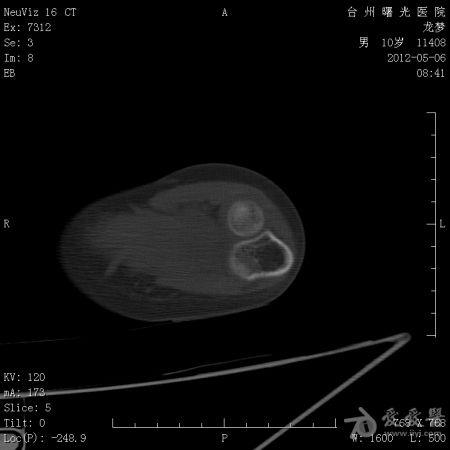

年龄:10岁主诉: 右上臂疼痛活动受限20余天现病史: 20余天前摔伤致右肘部疼痛活动不利,曾在外院治疗,X线:右肘部未见明显异常。肘关节活动尚可,于活血化瘀,消肿止痛治疗。20余天疼痛未见明显好转,肘关节活动不利,***就诊。既往史: 既往健康

体格检查: 一般状况好,发育良好,营养中等。头颅五官胸腹未见异常。右肘部,右上臂下端肿胀,压痛、纵向叩击痛(+),局部肤温增高。肘关节固定于约40°,背伸约20°,肘屈约100°,表面无血管充盈,无色素沉着。右上肢皮肤感觉正常,右桡动脉搏动正常。

初步诊断: 左肱骨下端骨肿瘤X线检查显示左肱骨中上段有虫蚀样 低密度改变,局部硬化,可见骨膜反应,病理性骨折鉴别诊断: 动脉瘤样骨囊肿,骨结核诊疗过程:

讨论内容:患者病史极短,摔伤后检查未见明显异常,初次就诊,复诊时间间隔约16天,未留下初次就诊的X线资料,仅感觉肱骨下端较上段骨密度稍减低。

骨肉瘤多见于小儿,多发生于干骨端,常见于股骨远端和胫骨近端。骨肉瘤的X线表现:⒈骨质破坏⒉肿瘤骨⒊肿瘤软骨钙化⒋软组织肿块⒌骨膜反应和Codman三角。动脉瘤样骨囊肿多发生于10-20岁,可发生生于长骨和脊柱。动脉瘤样骨囊肿的X线表现为长骨干骺端的溶骨性、偏心性骨破坏,其偏心向外突出如气球状膨胀,病变呈局限性透亮区,边界清楚,边缘有狭窄的硬化带,其中有不规则的分隔,呈蜂窝状。位于骨中心者,向周围扩张膨胀,呈卵圆形,与骨的纵轴一致。囊肿表面有一薄的骨壳,可有一层薄的骨膜反应。位于脊椎的病变多在脊突、椎板、横突上,亦可膨出于骨外。 根据以上特点和本病例的表现,骨肉瘤可疑。